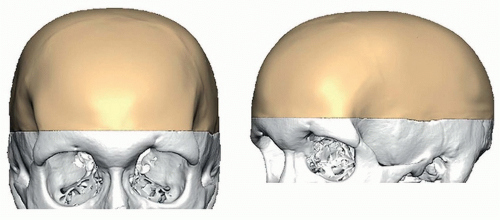

High-resolution (slices of 1 mm or less) 3D CT scan is essential to evaluate the size and thickness of the skull defect as well as for computer design of the reconstructive implant (FIG 1).